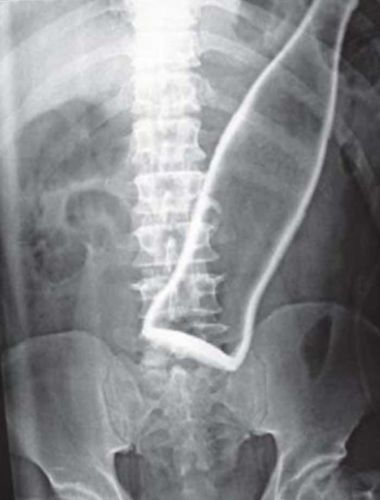

Garrafa de refrigerante